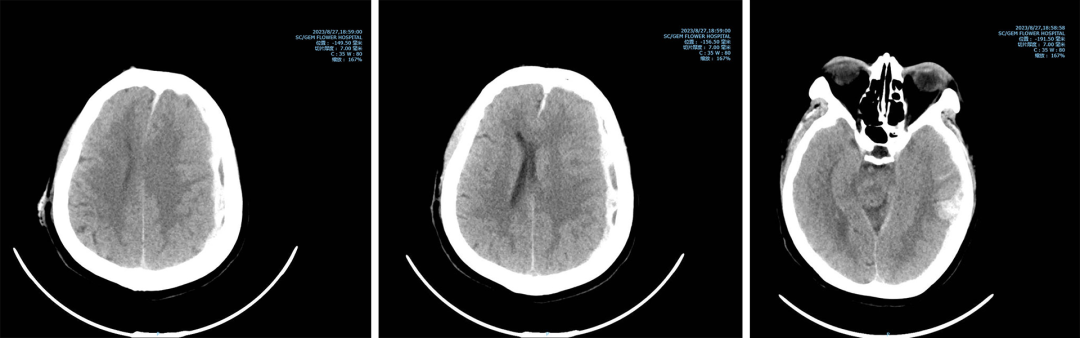

术前脑疝、急性硬膜下血肿、脑内血肿形成

第一次手术,时间就是生命,每一秒的流逝都紧紧牵动着全家人的心弦。神经外科医生团队凭借着丰富的经验和冷静的判断,迅速制定出详尽的手术方案,并以最短的速度将老人从死神的魔掌中奋力夺回。